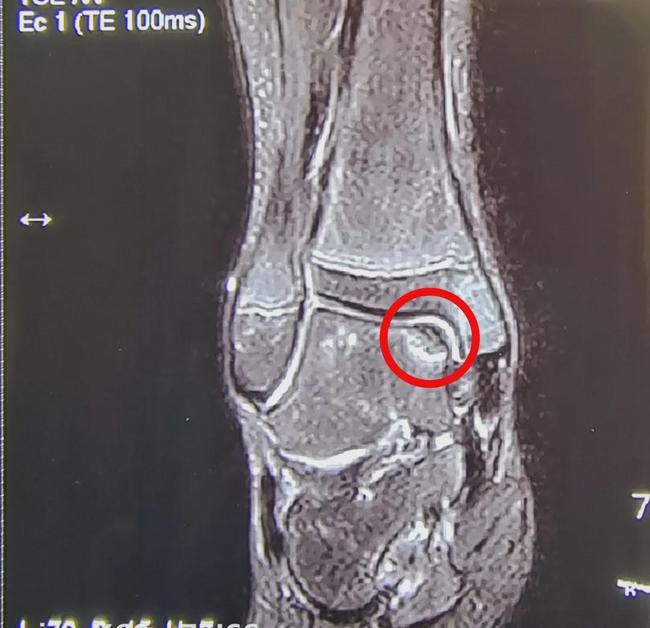

根据核磁共振的显示软骨损伤程度分为5级(Hepple分级):0级正常,1级软骨呈高信号但形态完整;2a级软骨损伤软骨下骨骨折伴有周围水肿,2b级软骨损伤软骨下骨骨折无周围水肿;3级软骨骨折上翘未发生移位,4级软骨骨折伴骨折片移位,5级软骨下骨囊性变形成(图2)

图2 根据核磁共振检查距骨骨软骨损伤的分型